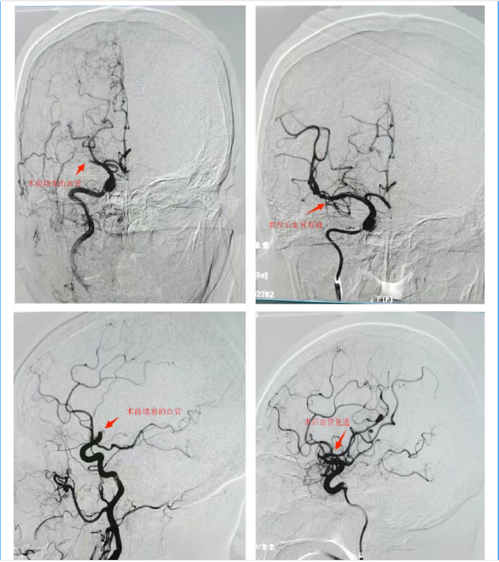

经桡动脉脑血管造影

急动脉瘤栓塞术脑梗死急诊取栓术后再通